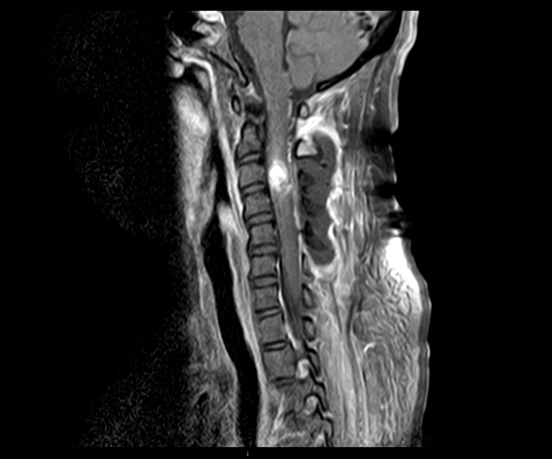

术前MRI提示C3-4髓内占位并破裂出血

术后MR复查结果